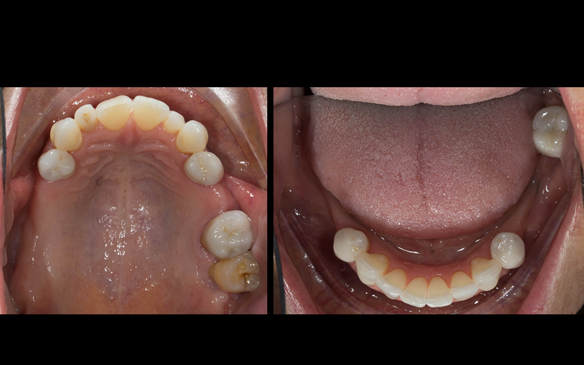

This newsletter describes in step by step detail Angela's transition through immediate partial dentures to crown supported definitive metal based dentures.

This 58 year old woman was referred to me by her general dental practitoner for treatment.

- Generalised Periodontitis; Stage 4, Grade C, Currently Unstable. Risk Factors: Type 1 diabetes. 16, 17 - hopeless prognosis. 14, 24, 26, 27, 34, 37, 44 - guarded prognosis

The clinical situation and treatment process is shown in detail below with photographs. I (Finlay Sutton) provided the clinical work and Rowan Garstang provided the technical work.